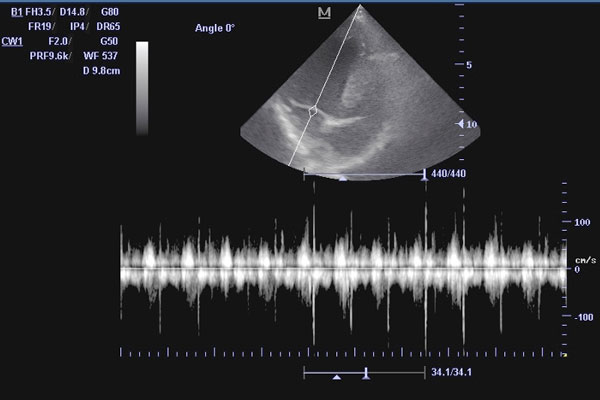

Допплеровская эхокардиография. Включает режимы цветового и спектрального Допплера. Это критически важный этап, поскольку он позволяет оценить скорость, направление и характер кровотока внутри сердца и крупных сосудов. С помощью Допплера выявляют турбулентные потоки, которые могут указывать на пороки клапанов или наличие патологических сообщений (шунтов).

ЭХО сердца при выявленном шуме у кошки

Пациент: Василий, кот, 6 лет

Жалобы: Обращение на плановый осмотр. При аускультации — мягкий систолический шум на верхушке сердца. Сам кот активный, дыхание ровное, кашля нет.

Диагноз: Незначительная митральная регургитация, минимальная дилатация левого предсердия. Фракция выброса по Симпсону — 72% (в норме). Диагноз: начальные признаки митральной недостаточности (стадия B1).

Что дало ЭХО: ЭХО сердца позволило точно оценить гемодинамику, исключить гипертрофическую кардиомиопатию и определить стадию заболевания. Это дало возможность начать профилактическое наблюдение без медикаментов.

Результат: Василий находится под регулярным контролем (раз в 6 месяцев). Через год — стабильные параметры, без прогрессирования. Владельцы информированы о признаках тревоги и важности профосмотров.